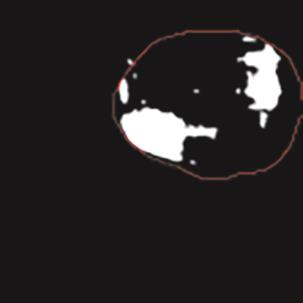

乳腺癌是全球女性最常见的恶性肿瘤之一,准确的病变分割对于乳腺癌的早期诊断与治疗具有重要意义。然而,由于病变形态的多样性以及超声成像机制的复杂性,现有基于深度学习的乳腺超声图像病变分割方法在分割准确性方面仍面临巨大挑战。为进一步提升乳腺超声图像中病变区域的分割精度,该文基于经典U-Net架构,提出了一种新型乳腺超声图像病变分割网络(CWSASKM-BBAM-Net)。首先,在网络中引入逐通道空间自适应选择核卷积模块(CWSASKM),根据不同通道的语义特征为每个空间位置自适应选择感受野大小,以增强多尺度信息的建模能力;然后,引入双向边界感知机制(BBAM),通过融合正向与反向注意力,对目标显著区域及其边界进行协同建模,同时逐步提升对非显著区域与病变区域的区分能力,以进一步强化边界信息的表达;最后,在3组公开乳腺超声图像数据集(BUSI、UDIAT和STU)上开展分割实验。结果表明:该方法在数据集BUSI上的杰卡德指数、精确率、召回率和Dice相似系数分别为71.97%、82.85%、81.40%和80.44%,较次优方法分别提升1.69、1.05、1.28和1.84个百分点;在数据集UDIAT上,这4项指标分别达到78.14%、88.31%、86.73%和86.10%,较次优方法分别提升了2.75、2.04、0.56和2.01个百分点;在外部数据集STU上,该方法也取得了优于其他方法的整体表现。实验结果表明,CWSASKM-BBAM-Net在乳腺超声图像分割任务中展现出更优的整体性能。